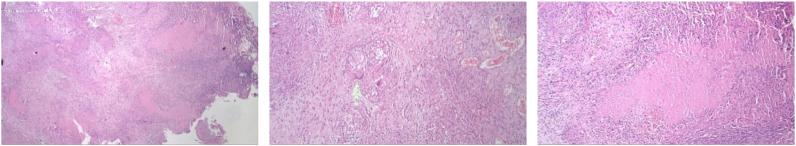

First case, a 22-year-old male, presenting with abdominal pain, underwent exploratory laparotomy, biopsy, right hemicolectomy, and anastomosis end-to-side to the transverse ileocolical region due to partial ileus obstruction from caecal tumor. The second and third cases, a 27-year-old and 39-year-old females, both presenting with abdominal pain and distension, underwent exploratory laparotomy, adhesiolysis and biopsy. Histopathological examination in all three cases showed chronic granulomatous inflammation caused by TB. All three patients were diagnosed as ITB and received 6 months of anti-tuberculosis drug (ATD).

Intestinal TB most commonly affected region is the ileocaecal, accounts for 64% of the incidence of gastrointestinal TB. The main reasons for the predilection of ileocaecal region are due to relatively longer faecal static, the abundant of lymphoid tissue, a neutral pH environment and absorptive transport mechanisms that allow swallowed mycobacterium to be absorbed. Intestinal TB may pose similar symptoms as those found in pulmonary TB, yet patients most commonly presenting with abdominal pain. Bacteriological signs and histopathological findings are gold standard for ITB diagnosis. Therapy for ITB includes pharmacological ATD and surgical therapy.